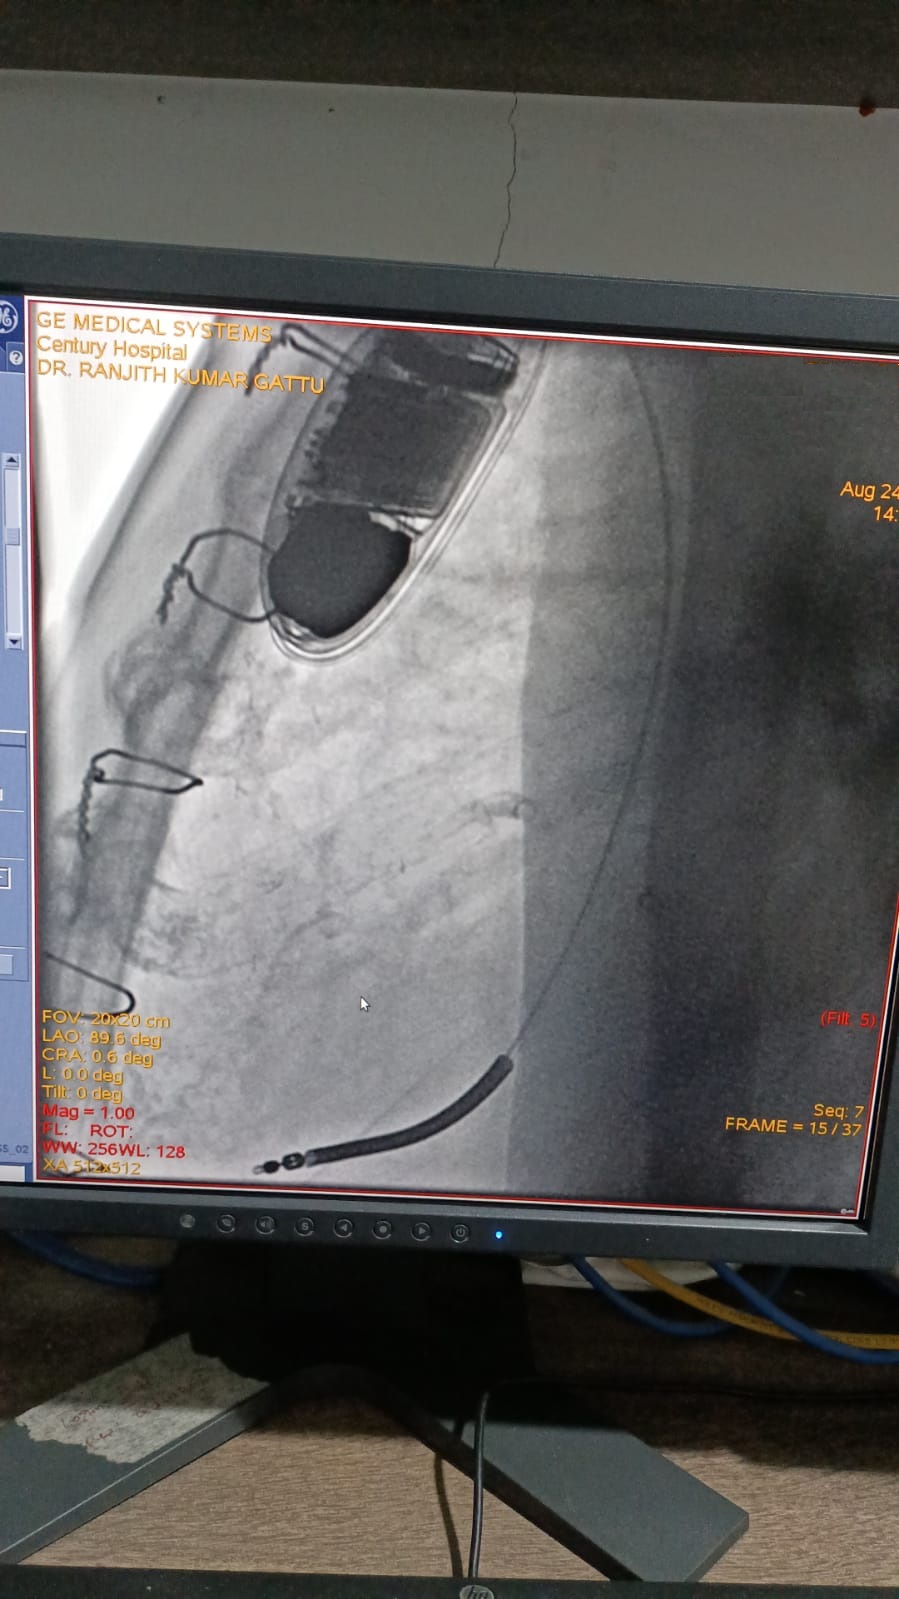

Catheter ablation of arrhythmias

Left Coronary Diseased Artery